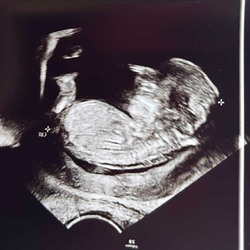

Ik heb de mijne gisteren laten zetten maar heb er nog geen reactie van #32 weken